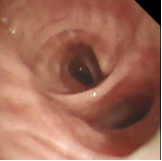

术前支气管 术中改变 术后支气管